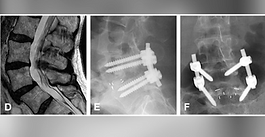

A comparative cadaveric biomechanical study of bilateral FacetFuse® transfacet pedicle screws versus bilateral or unilateral pedicle screw-rod construct

Teaching Case of the Week: SI Joint Fixation

Lessons from a Sacroiliac Joint Fusion